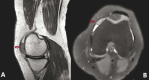

Giant cell tumors of the synovial membrane are benign but locally aggressive lesions that primarily affect synovial joints. Histologically, they are characterized by the proliferation of histiocytes, multinucleated giant cells and prominent hemosiderin deposition. Clinically, patients often experience joint pain, swelling and restricted movement, which can significantly impact their mobility and quality of life. Traditionally, open surgical excision has been the standard approach for managing these tumors. However, advancements in minimally invasive techniques, particularly arthroscopic surgery, have emerged as effective alternatives. Arthroscopy offers several benefits, including reduced postoperative pain, quicker recovery and minimal surgical trauma, while still allowing for complete tumor removal. This article presents a case of a giant cell tumor of the synovial membrane in the knee of a female patient, highlighting the successful use of arthroscopic treatment and the favorable postoperative outcomes. By presenting this case, we aim to emphasize the growing role of arthroscopic intervention in managing these tumors, further supporting its integration into clinical practice.